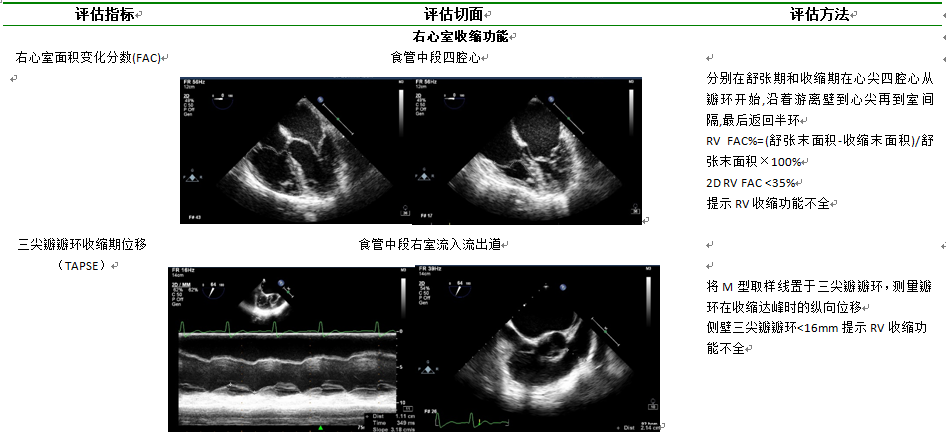

10.3.3右心室功能如表7所示

表7  右心室功能评估